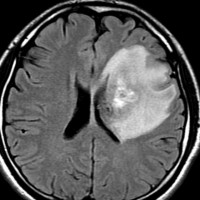

放射線治療13週目

右はガドリニウム増強です。ステロイドとグリセオールの点滴では制御できませんでした。悪性神経膠腫の病名で保険適応があるアバスチン(ベバシズマブ 10mg / kg)の投与を開始しました。